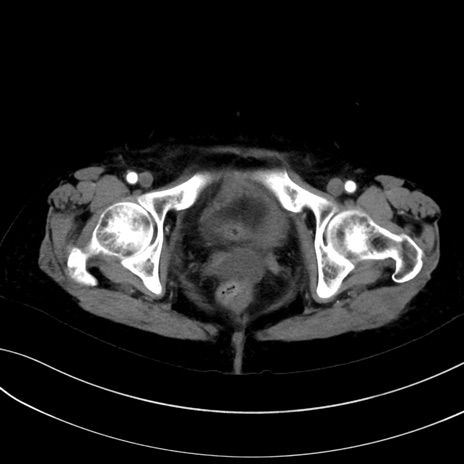

(冠状断像)1日半後